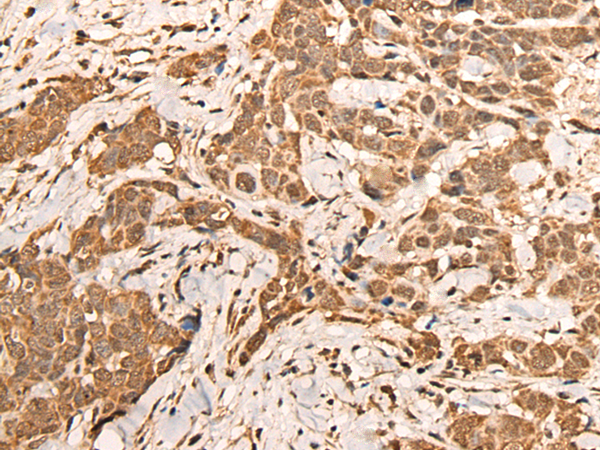

IHC positive control: |

Human thyroid cancer and human cervical cancer |